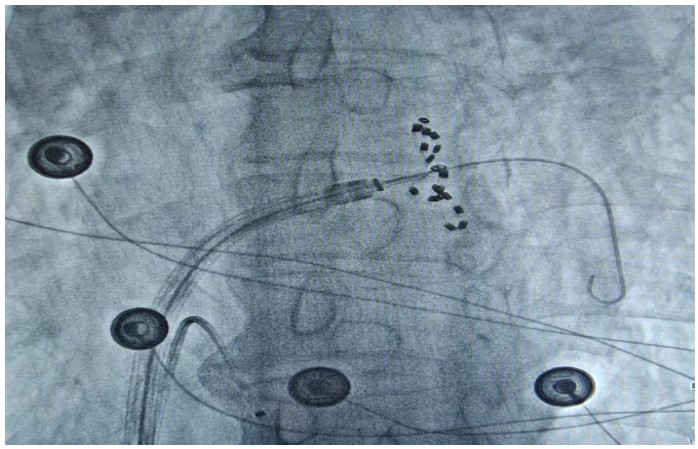

通訊員何紅丹報道:2025年1月17日,衡陽市中心醫(yī)院心血管內科趙慶禧主任醫(yī)師團隊與心血管內科電生理團隊協(xié)作���,在全麻下成功為一名72歲的男性患者實施了陣發(fā)性房顫FARAPULSE脈沖電場消融手術���。此次手術為目前全球最先進的PFA消融導管上市后全國首批臨床應用��,在湘南地區(qū)首次開展���,能更精準地作用于目標區(qū)域�����,減少對周圍組織的損傷����,極大程度降低并發(fā)癥的發(fā)生,具有更高的安全性��。

趙慶禧介紹�����,房顫是常見于老年人的心臟問題��,通俗的講就是心臟“亂跳”�����。發(fā)生房顫時患者心慌心悸難忍�����,極易誘發(fā)腦卒中等惡性后果��,嚴重危害生命健康��。目前�����,房顫的治療方法包括藥物治療和傳統(tǒng)導管消融。相較于藥物治療和傳統(tǒng)導管消融����,脈沖電場消融可選擇性的損傷心肌,而保留血管��、神經(jīng)及心臟周圍組織��。更快的消融脈沖電場消融(PFA)技術是最新的消融技術�,它能通過高壓電脈沖,實現(xiàn)消融點細胞凋亡的目的���,達到抑制紊亂心律發(fā)生的作用���。與傳統(tǒng)消融技術相比,脈沖電場消融具有更高的組織選擇性��、更快的消融速度以及更低的貼靠要求�,成為臨床迫切需要的突破性創(chuàng)新治療方法�����,為患者帶來了新的選擇和新的希望。